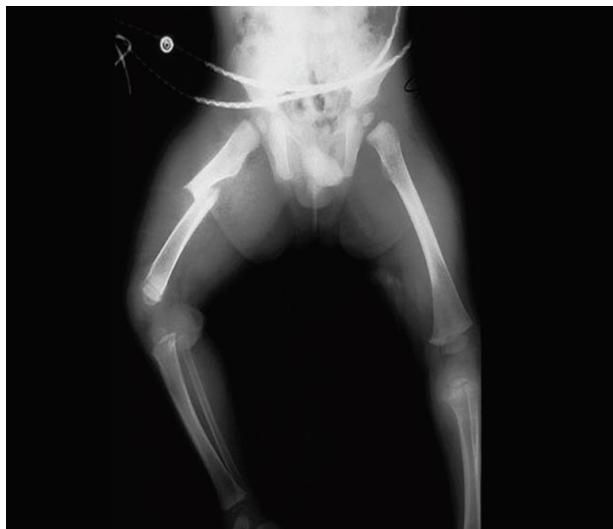

Child Abuse

- Suspicion Factors:

- Multiple bruises in different stages of healing (different colors).

- Injuries in soft tissues or unusual areas (not over bony prominences).

- Specific patterns: loop marks (belt/cord), fist or pinch marks, cigarette burns.

- Spiral fractures in non-walking children.

- History inconsistent with the injury.

- Management:

- Manage as a trauma patient.

- MANDATORY reporting to social workers and child protection teams.

- Admission for safety if necessary.